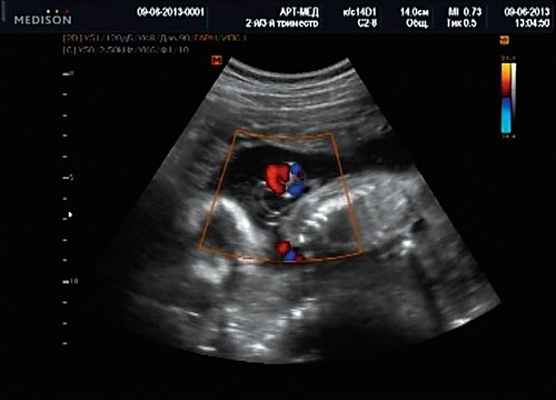

Беременная М., 21 года. Впервые обратилась в клинику в срок 20 нед беременности. Исследование проводилось на аппарате SonoAce-R7 (Samsung Medison) с использованием режима поверхностной объемной реконструкции 3D/4D. При изучении позвоночника плода в трех плоскостях костных деформаций не выявлено. В грудном отделе позвоночника обнаружено тонкостенное кистозное образование с анэхогенным содержимым, стебельчатой формы (рис. 10-12). Степень "прозрачности" содержимого была выше околоплодных вод, что позволяло идентифицировать его как ликвор. В проекции грыжевого выпячивания располагалась петля пуповины, дифференциальную диагностику которой без труда удалось провести с помощью ЦДК (рис. 13).

Рис. 13. Петля пуповины в режиме ЦДК.

У плода наблюдалась выраженная гидроцефалия, обусловленная синдромом Аронольда - Киари II (рис. 14, 15).